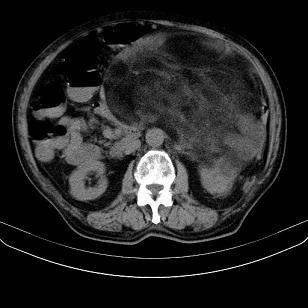

标题: CT21671:男,88岁,左上腹包块 [打印本页]

标题: CT21671:男,88岁,左上腹包块

患者因咳嗽而住院,自觉右上腹包块,无其他不适。

脂肪肉瘤,应测ct值。

考虑腹膜后脂肪肉瘤可能性大。 畸胎瘤不除外。